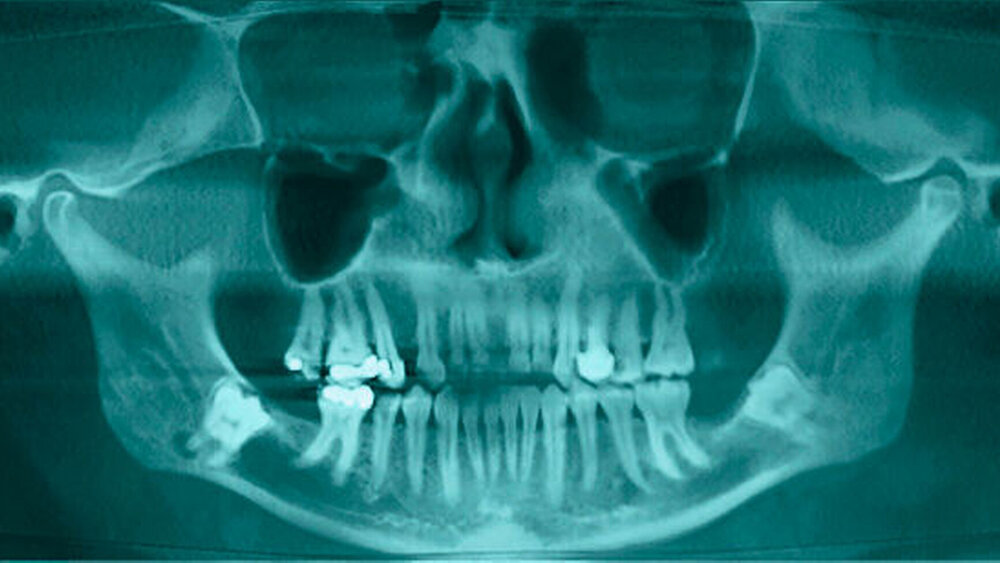

Eine 47-jährige Patientin wurde zur Entfernung der komplett retinierten Zähne 38 und 48 überwiesen. An der Wurzelspitze des Zahnes 48 fiel zusätzlich eine periradikuläre Transluzenz auf, die zur Indikationsstellung der Entfernung der Zähne führte (Abbildungen 1 und 2).

In der aus der digitalen Volumentomografie herausgerechneten Panoramaschichtaufnahme analogen Darstellung kann man schön die Alteration des Nervverlaufs in unmittelbarer Nachbarschaft zu den Weisheitszähnen erkennen. Der Nerv taucht von proximal kommend noch hinter dem Zahn liegend in die Tiefe, um dann auf Höhe der distalen Wurzel wieder in einem geraden Verlauf nach vorne weiter zu ziehen.

Eine Verletzung des Nervus alveolaris inferior bei Weisheitszahnentfernung findet sich überproportional häufig in Fällen, in denen auf der Panoramaschichtaufnahme Zeichen zu erkennen sind, wie eine Veränderung des Verlaufes des Nervus alveolaris inferior (Abbildungen 1 und 2), bei überlagerungsbedingter erhöhter Transluzenz im Bereich der Überprojektion von Wurzel und Nerv und bei Unterbrechung der kortikalen Begrenzung des Nervkanals [Blaeser et al., 2003]. Alle diese Kriterien lagen im vorliegenden Fall vor. In der weiterführenden digitalen Volumentomografie ist zu erkennen, wie der Nerv zwischen den Wurzeln liegend hindurchzieht.